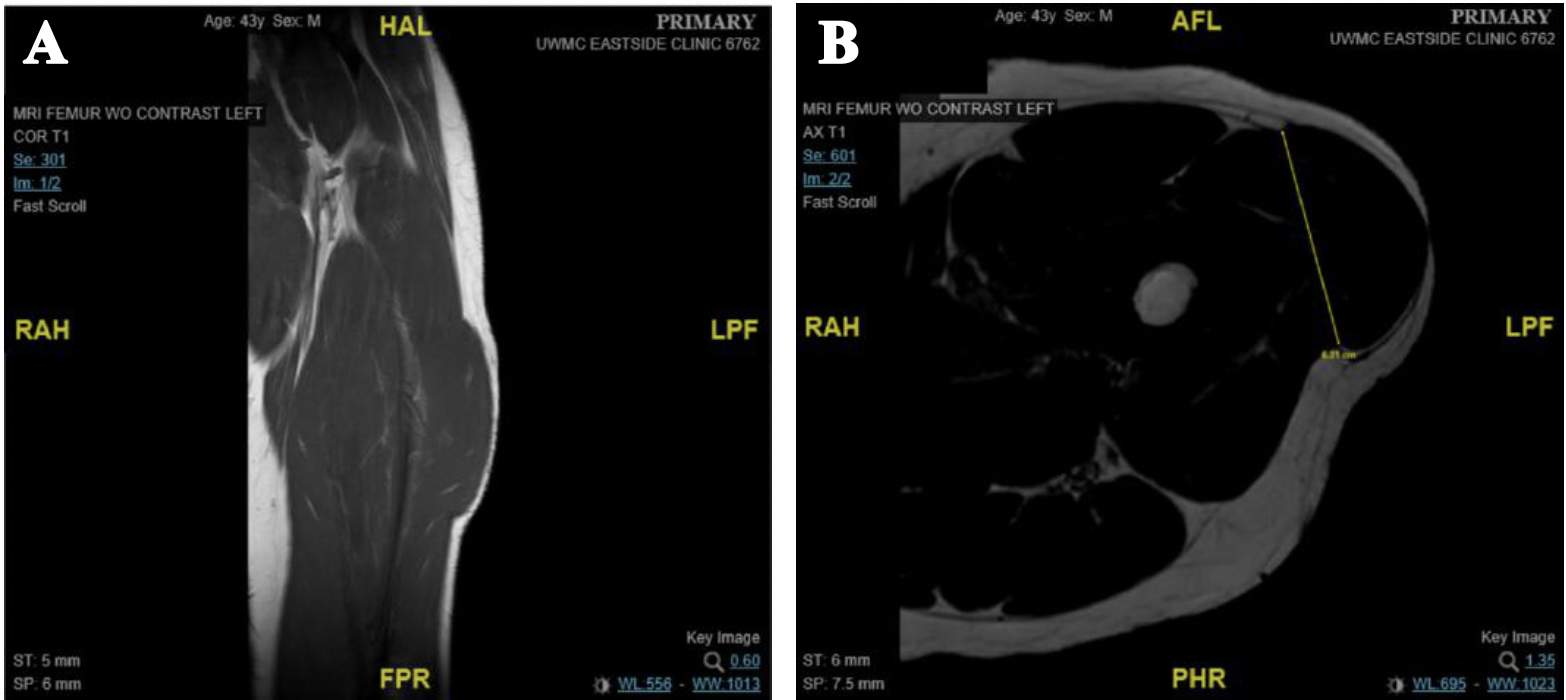

A 43-year-old male was referred for repair of a left thigh fascial defect associated with painful muscle herniation. Two years prior to consult the patient had a left orbit osteoma compressing his eye that was removed endoscopically and complicated by a postoperative cerebrospinal fluid leak. Treatment at the time proceeded with skull base reconstruction using fascia lata from the left thigh. Repair was successful, but the patient developed a vastus lateralis muscle herniation at the donor site within a short time after his surgery. A primary repair of the fascial defect was attempted not long after but proved unsuccessful and subsequent magnetic resonance imaging (MRI) confirmed a persistent fascial defect (Figure 1). The symptoms were primarily numbness, a noticeable bulge that made the patient self-conscious, muscle spasms, and bouts of debilitating pain of the lateral thigh with walking or strenuous weight-bearing activity. Scar tissue tethering skin to the underlying muscle caused further distress by pulling skin in and out with basic movements of the leg (Figure 2). Due to these symptoms, the patient was unable to ambulate for extended periods of time and lost his employment.

Figure 1. MRI shows (A) defect in the facia lata overlaying the vastus lateralis, with herniation of the proximal vastus lateralis muscle and (B) defect measures 6.2 cm (axial plane) x 13 cm (craniocaudal plane) at time of consult.